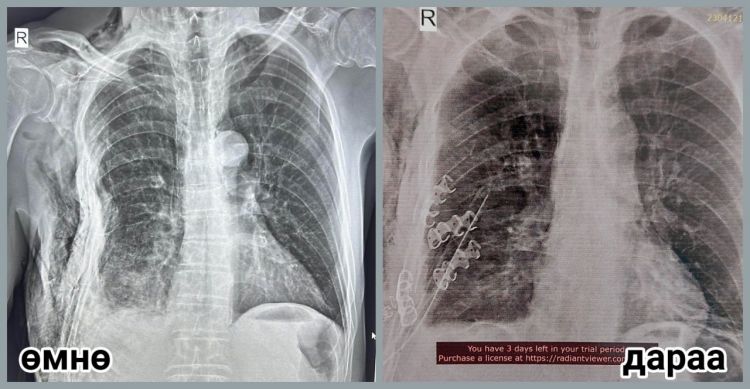

Гэмтэл согог судлалын үндэсний төвийн Хавсарсан гэмтлийн тасгийн эрхлэгч, их эмч П.Баярсайхан, мэс заслын их эмч С.Мөнхлхагва,...